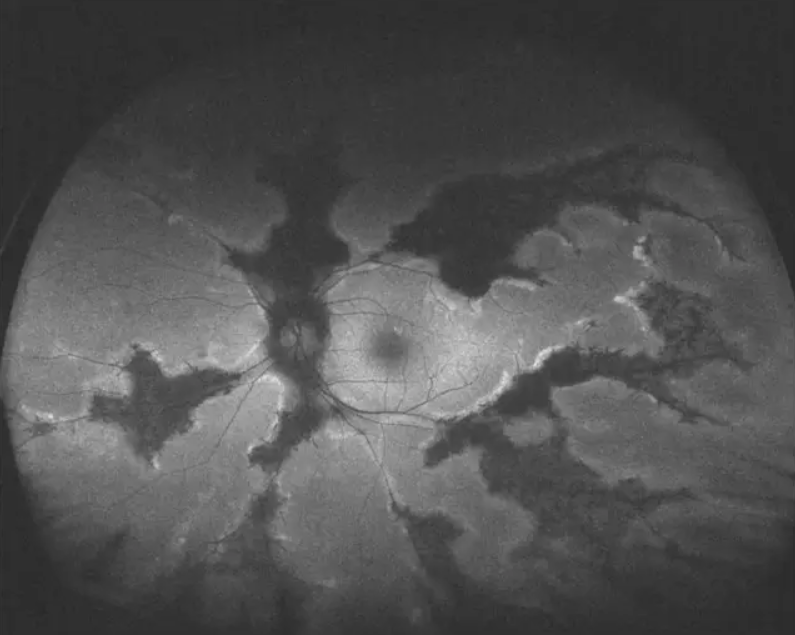

▲AFC-210超广角眼底彩照,在免散瞳情况下即可拍摄,患者无需散瞳,瞳孔直径大于2mm即可检查。

▲AFC-210超广角自发荧光。同样是在免散瞳的情况下即可进行拍摄,使用绿激光进行激发,对黄斑的伤害更小。